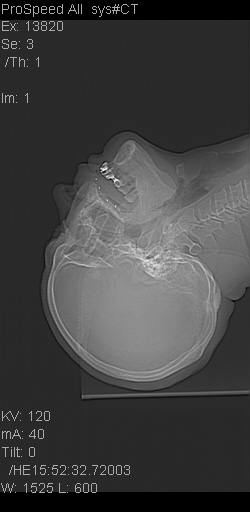

患者,男,以头面部外伤后头疼1小时为主诉入院,患者1小时前被他人打伤头部及左侧面部,眼睑无水肿,左侧面部肿胀压疼,未触及骨擦音。专科检查:耳鼻喉未见异常。

ct:平扫+冠扫:双侧鼻骨对比,冠扫s6#示右侧鼻骨尖部可见线状低密度影,边缘光滑,并见硬化.软组织未见肿胀.